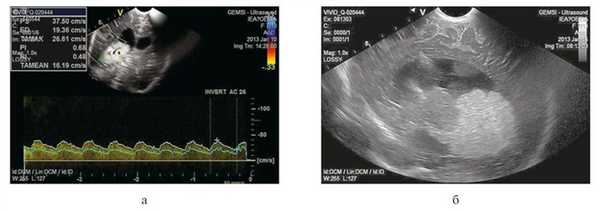

По результатам последних МРТ-исследований головного мозга решено было произвести удаление опухоли с применением транскаллезного доступа с эндоскопической ассистенцией. Учитывая мигрирующий характер опухоли и для уточнения локализации питающего опухоль сосуда непосредственно перед оперативным вмешательством проведена нейросонография в режиме допплерографии. Выявлен крупный питающий сосуд — проходящая в толще опухоли хориоидальная артерия, а также миграция опухоли в задний и нижний рог правого бокового желудочка (рис. 2).

Рисунок 2. Нейросонография в день операции. а — фронтальный срез в режиме допплерографии, видна ветвь хориоидальной артерии, ветвящейся в толще опухоли; б — сагиттальный срез: миграция ПСС в задний и нижний рог правого бокового желудочка (возраст ребенка 4 мес).